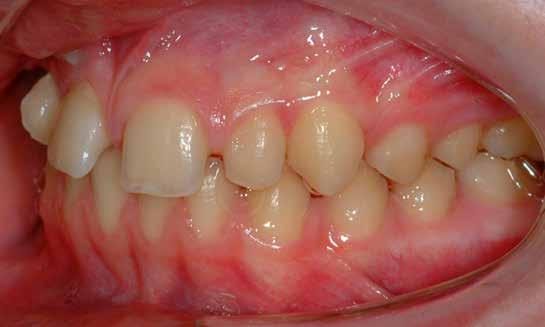

A szemfog oldalsó kismetsző helyére történő bemozgatása során a fog átalakítása javasolt a két fog eltérő morfológiai adottságai miatt (1. a-b. ábra). A fog kontúrozása, vagy úgynevezett formázása magába foglalja az approximális felszínek elcsiszolását, valamint a többi fogfelszín igazítását a kívánt fogformának megfelelően [1].

A kismetsző és szemfog klinikai koronái közötti eltérések a következőek: mezio-disztálisan keskenyebb oldalsó metsző, csücsök hiánya, egyenes éli lefutás, és a vesztibuláris felszín domborulata is kevésbé kifejezett [2,3]. A szemfoggal összehasonlítva, az oldalsó metsző rendszerint rövidebb és keskenyebb mind mezio-disztálisan, mind vesztibulo-orálisan. Az átformázott szemfog és az oldalsó metsző anatómiai alakja közötti egyezés függ az elülső zóna mint egység formájától is. Kataoke és Nishimura három alapformát határozott meg az elülső fogak tekintetében: négyszögletes, óvóid és háromszög formájú [4]. A frontfogak vesztibuláris felszínét a három kúp egységeként írják le (kúpos fejlődési mamelonok): meziális, disztális és centrális. A szemfogak esetén a három közül a központi a legdominánsabb, de nem ugyanez a helyzet az oldalsó metsző esetében. Háromszög alakú fogkorona esetén a meziális és disztális érvényesül jobban, négyszögletes formánál mindhárom egyenlő arányban domborodik, míg óvóid forma esetén a középső kerül túlsúlyba. Ennek megfelelően a szemfog csücskét el kell csiszolni, és kompozit felépítéssel az elülső anatómiai formához illő oldalsó metsző alakzatot kialakítani a szélső élek megfelelő hangsúlyozásával [5]. Amennyiben az elülső fogak formája háromszögletes, akkor kifejezett meziális és disztális felépítésekre lesz szükség. Négyszögletes forma esetén a szemfog meglévő centrális kúposságát kiegyensúlyozva építik fel a fogat. Az elülső fogak ovoid alakzata esetén a meziális és disztális kúposságot alig vagy egyáltalán nem hangsúlyozzák

1. a–b ábra